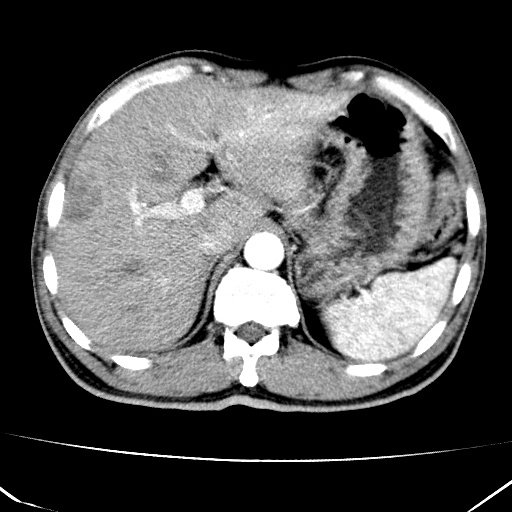

标题: CT17975:请求会诊。男、57岁。上腹部胀痛2天。临床诊断:糜 [打印本页]

标题: CT17975:请求会诊。男、57岁。上腹部胀痛2天。临床诊断:糜

肝脏多发类圆形低密度影,考虑肝脏转移瘤,肝胃韧带一淋巴结肿大,原发?胃癌?

考虑胃癌并肝脏及腹膜后淋巴结转移;不排除淋巴瘤。

肝内转移瘤,腹腔及腹膜后淋巴结转移。

考虑胃癌肝脏转移可能性大。应要求上腹部检查时常规准备。